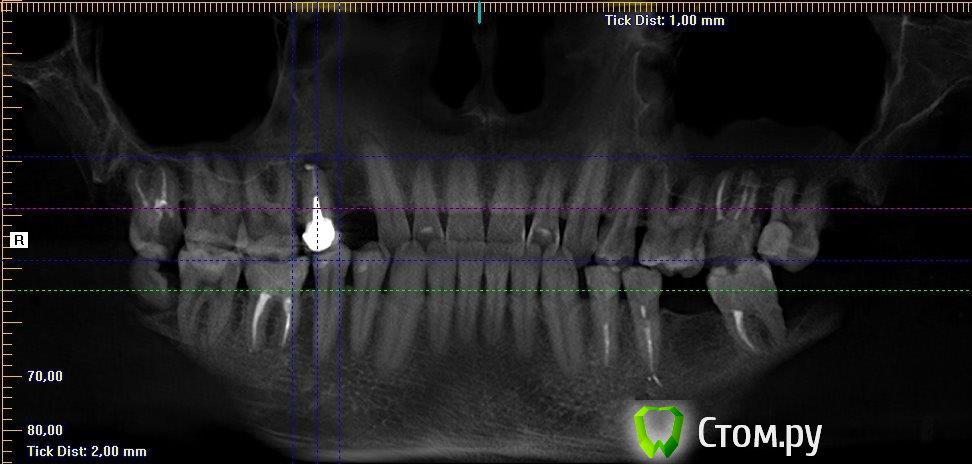

Таня-К Опубликовано 21 июня, 2014 Поделиться Опубликовано 21 июня, 2014 Уважаемые врачи, помогите, пожалуста, с выбором метода лечения 15 зуба.В разных клиниках предложены такие решения:1. Снятие коронки, удаление штифтовой конструкции, ревизия двоканального зуба,озонирование каналов перед пломбированием, пломба, временная коронка, постоянная коронка.2. Резекция верхушки корня с ретроградным пломбированием, костная пластика альвеолярного отростка.3. Удаление и имплантация.Какой метод лечения Вы считаете оптимальным с медицинской точки зрения?Большое спасибо всем. Ссылка на комментарий

Bier Опубликовано 22 июня, 2014 Поделиться Опубликовано 22 июня, 2014 если нёбно кариес корня, то удалять, если корень целый, то РВК с ретроградкой. Ссылка на комментарий